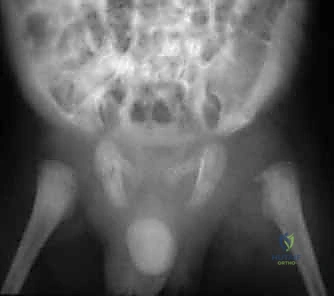

- الأشعة السينية (X-rays): تُجرى لاستبعاد وجود كسور أو أورام. في الأيام الأولى للالتهاب القيحي، قد تظهر الأشعة طبيعية، أو قد تظهر اتساعاً في المسافة المفصلية بسبب تجمع الصديد، أو خلعاً جزئياً لرأس الفخذ. التغيرات العظمية المدمرة لا تظهر إلا في مراحل متأخرة (وهو ما نسعى لتجنبه).